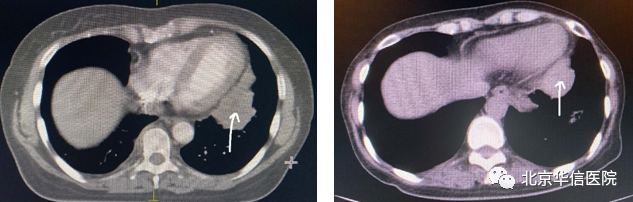

左侧心包旁放疗前后对比图,见箭头所示(左图为放疗前)